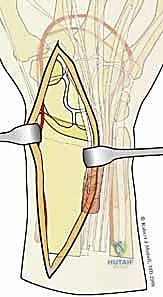

1. المداخل الجراحية (Surgical Approaches)

نظراً لأن الكسر يتم تثبيته من جهات متعددة، قد يستخدم الدكتور هطيف شقوقاً جراحية صغيرة ومدروسة بدلاً من شق واحد كبير.

* المدخل الأمامي (Volar Approach): للوصول إلى الحافة الهلالية والسطح الأمامي لعظم الكعبرة. يتم إبعاد الأوتار والأعصاب (مثل العصب المتوسط) بعناية فائقة.

* المدخل الظهري أو الجانبي (Dorsal/Radial Approaches): شقوق صغيرة إضافية للوصول إلى شظية العمود الكعبري أو الجدار الظهري، مع الحفاظ التام على الأوتار الباسطة.